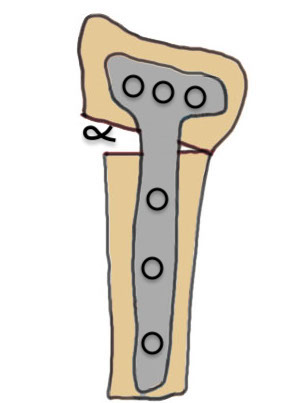

Volar opening wedge

Advantage

Volar approach and plate

Disadvantage

May require dorsal approach to bone graft

Technique

Vumedi volar osteotomy for distal radius fracture

Bed of FCR approach

- release brachioradialis

- protect structures with retractors

- perform osteotomy parallel to articular surface

- sufficient distal bone for screw fixation

- correct distal radius in two planes

- apply volar plate

- bone graft defect through radial aspect of wound

+/- dorsal approach to insert bone graft